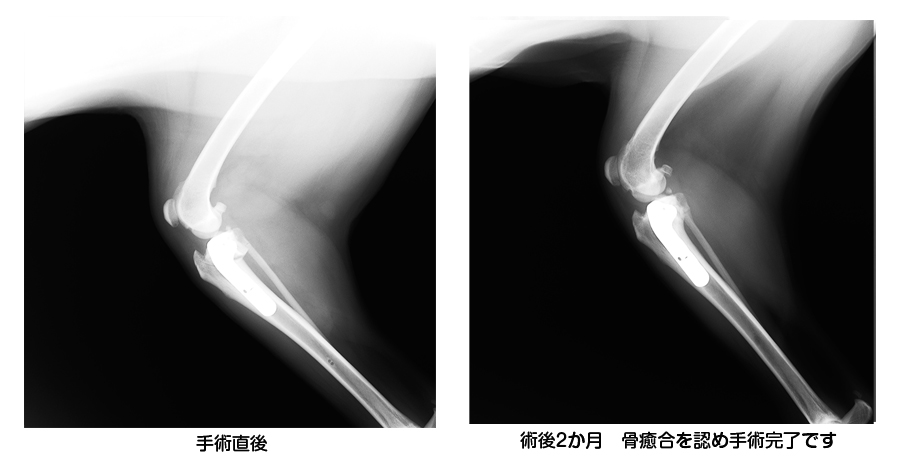

◆ラブラドールレトリバー 7歳10カ月 避妊メス 31㎏

TPLO(脛骨高平部水平化骨切術)を実施

◆経過